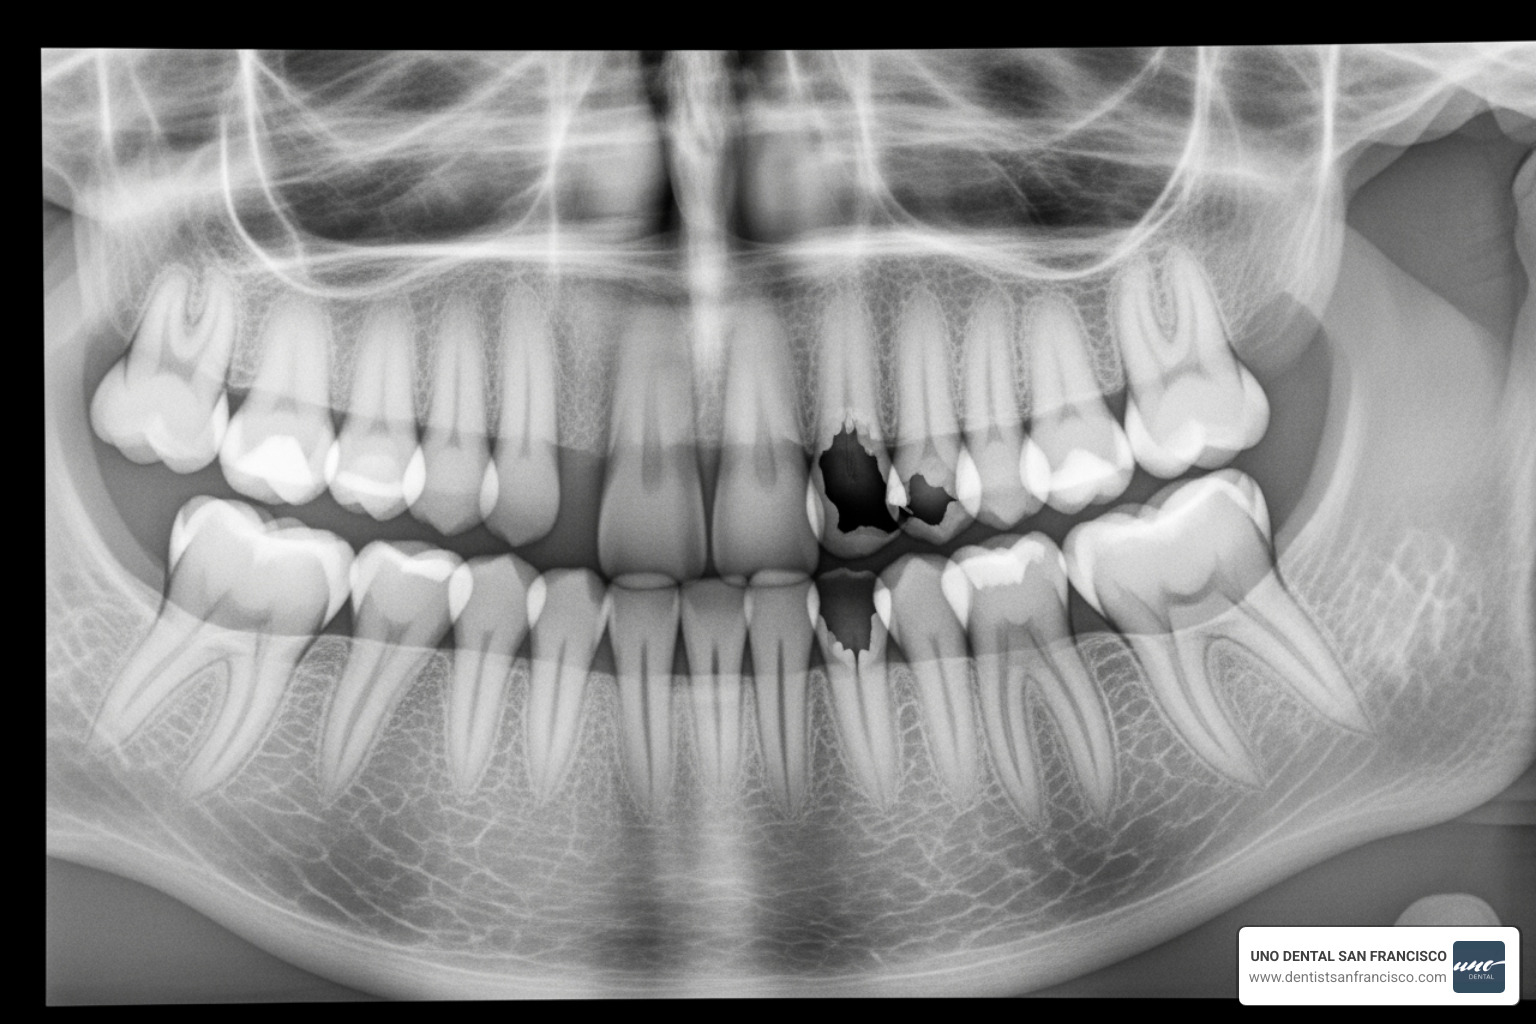

- Visible holes or dark spots: Classic indicators of tooth decay that may require a filling.

- Fractured or chipped teeth: Even minor cracks can worsen over time and compromise the tooth.

- Persistent toothache or sensitivity: Sharp or throbbing pain, especially when chewing, can signal decay, a crack, or an infection.

- Tooth decay (caries): The most common issue, treated by removing decay and placing a filling.

- Advanced Diagnostics: We use tools like digital X-rays and 3D imaging (CBCT scans) for a complete view of your oral structures. Intraoral cameras allow you to see what we see, helping you understand your health.